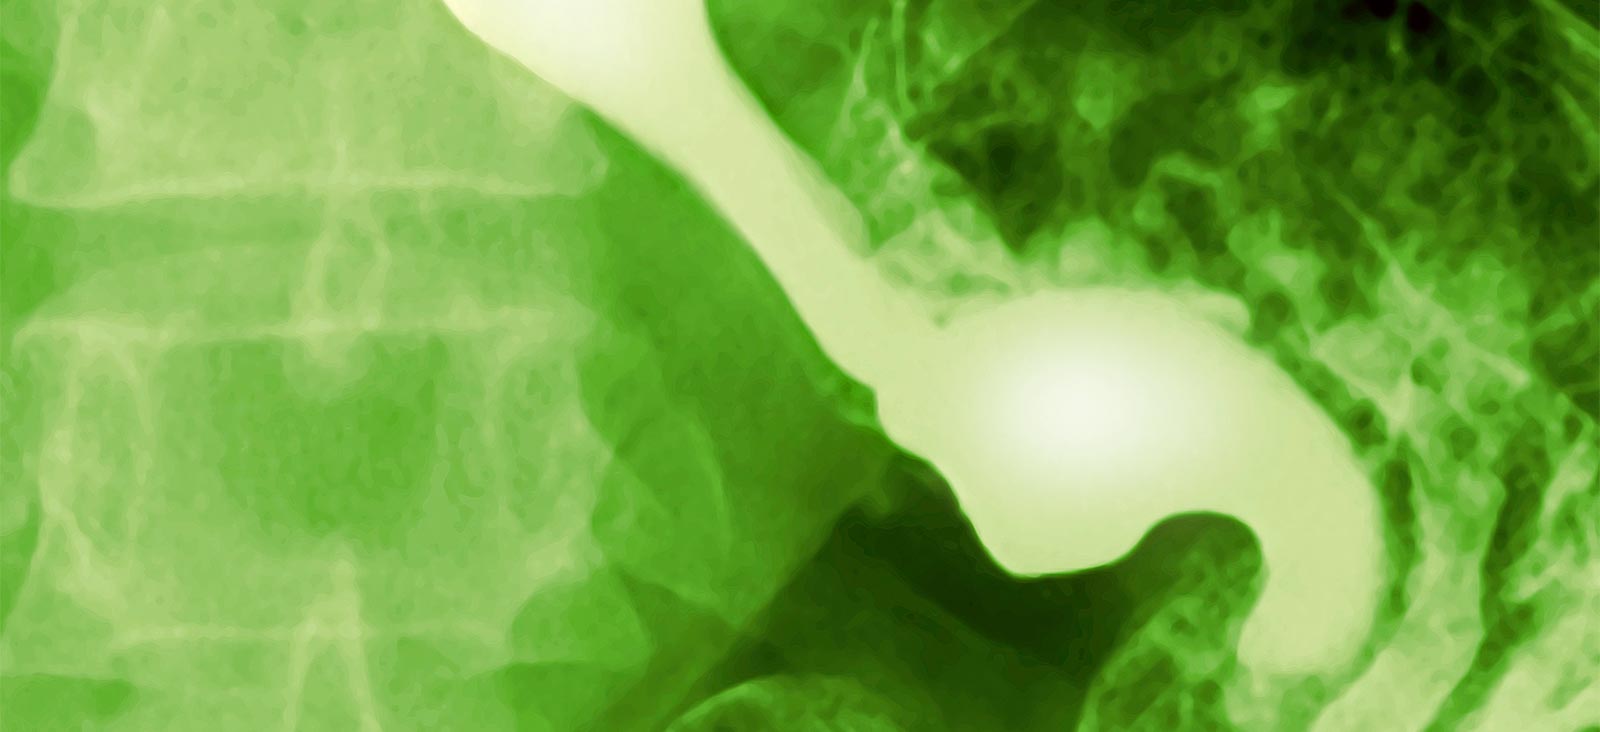

Esophageal perforation is a hole in the esophagus – the muscular tube our food travels through on its way from the mouth to the stomach – that allows saliva, liquids, and food to spill into the thoracic cavity or abdomen. It’s an uncommon but serious medical condition.

Perforation of the esophagus is usually caused by prolonged vomiting and forceful retching, the ingestion of bones, or after surgery or instrumentation of the esophagus (endoscopy and biopsies). The perforation can occur at any point along the esophagus, including the neck, chest, and abdomen.